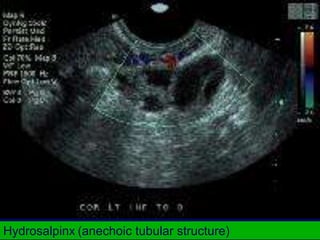

Hydrosalpinx (anechoic tubular structure)